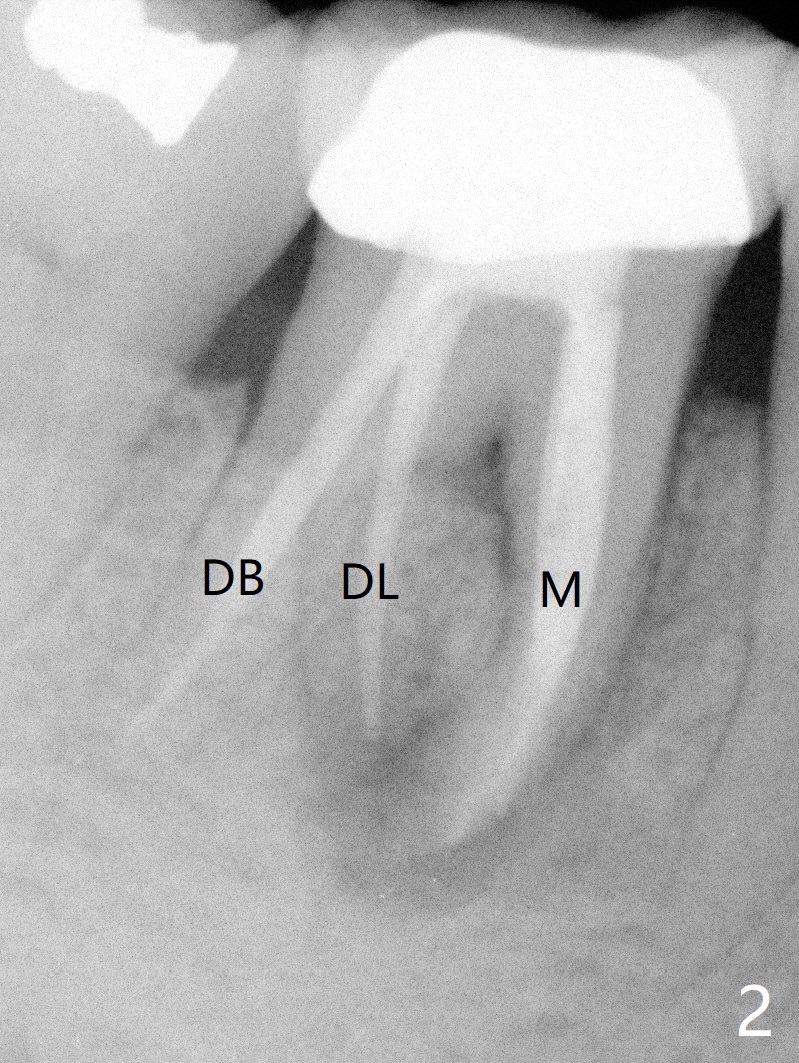

A 55-year-old woman has severe bone loss (Fig.1 with buccal and lingual fistulae) around the mesial (M in Fig.2) and distolingual (DL) roots. If there is a septum after extraction (Fig.3 S), osteotomy will be established in the septum to enhance primary stability (Fig.4). When the septum cannot be saved (Fig.5), osteotomy is to be initiated in the septal slope oblique (Fig.6 <). The osteotomy will be straightened once an entry is made (Fig.7). The initial osteotomy is slightly distal, since as osteotomy increases (Fig.8 blue), it tends to shift mesial (arrow). In addition, the apex of the 2nd bicuspid tilts distal (yellow dashed line). Depth of osteotomy is 20 mm (crest, Fig.9) or 18 mm (septum) so that 8 mm of the native bone can be obtained with 3 mm clearance from the Inferior Alveolar Canal (red dashed line). PRFx2 is required (seems not done).